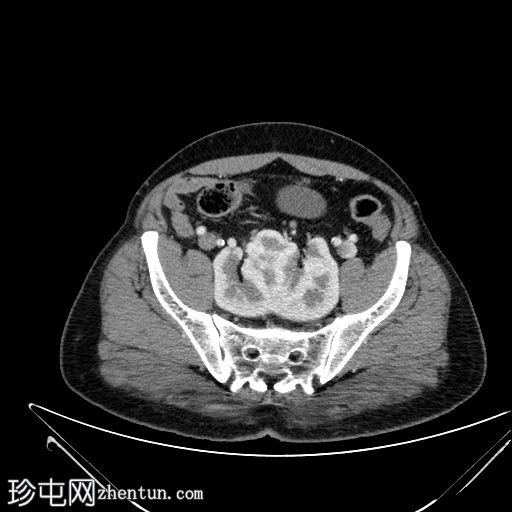

CT

轴位

平扫

冠状位

轴位增强扫描(门静脉期)

冠状位增强扫描(门静脉期)

三维

VR

冠状位肾盂排泄期

双肾上极和下极融合,形成扁平肾,在轴位、冠状位和三维图像上均可见。

有两条独立的输尿管,左右输尿管分别独立引流至膀胱。

未见结石或反流压力改变。

本病例展示了扁平肾,这是一种解剖变异,其特征是双肾上极和下极完全融合。这与马蹄肾不同,马蹄肾仅下极通过峡部连接。

虽然扁平肾可能是一种偶然发现,但评估是否存在相关并发症(如肾结石和反复

泌尿

道感染)非常重要。